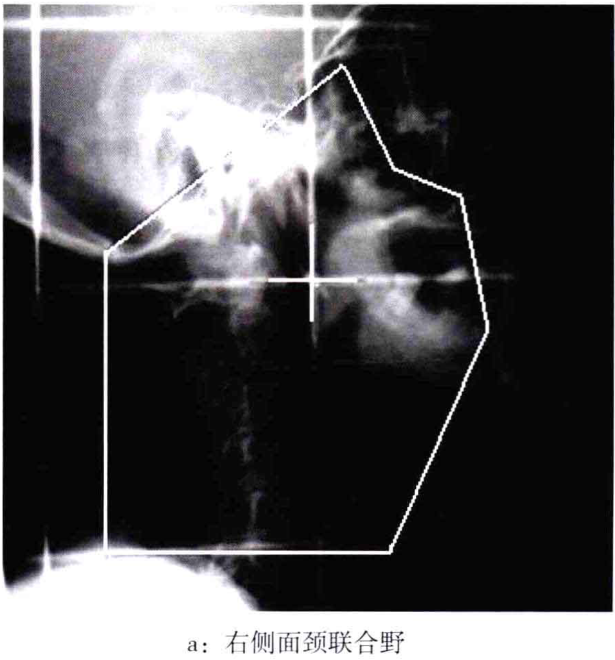

4、1号震台:这个词可能与地震监测、地质研究等领域的设施或项目有关,地震监测对于预防自然灾害、保障人民生命财产安全具有重要意义。

3、地震监测与防灾减灾:1号震台可能涉及到地震监测技术的研究和应用,通过监测地震活动,预测地震灾害,为防灾减灾提供有力的技术支持,保障人民生命财产安全。